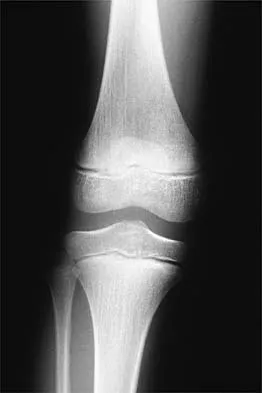

Figure 24 shows the radiograph of a 10-year-old boy who sustained a valgus injury to the knee. Examination reveals grade III medial laxity. Initial management should consist of